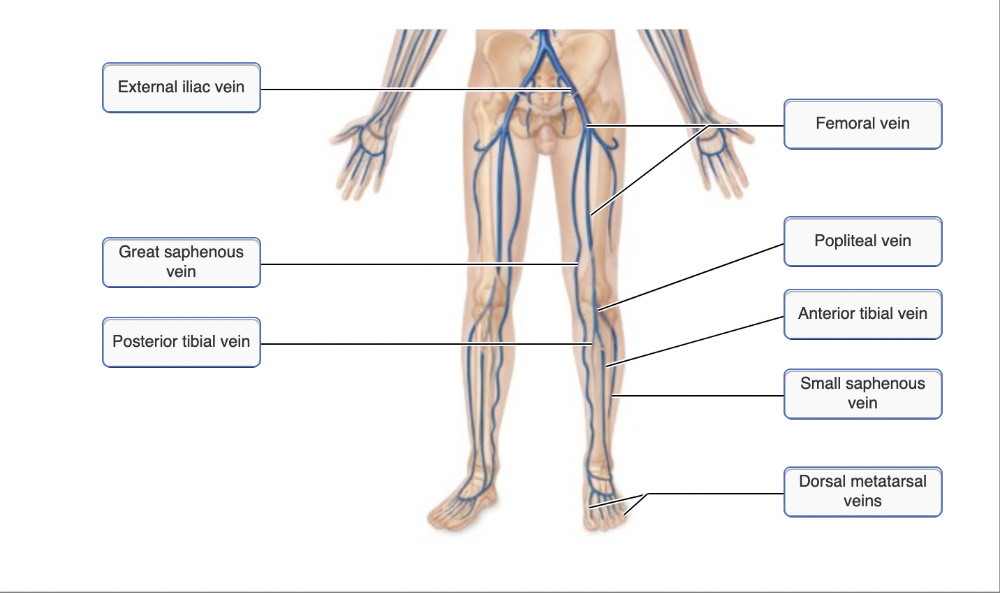

Drag the appropriate labels to their respective targets.

Name the vein at A.

- femoral vein

- small saphenous vein

- fibular vein

- external iliac vein

femoral vein

Ex.

The femoral vein is the largest vein draining the lower extremity. It unites with other veins to form the external iliac vein.